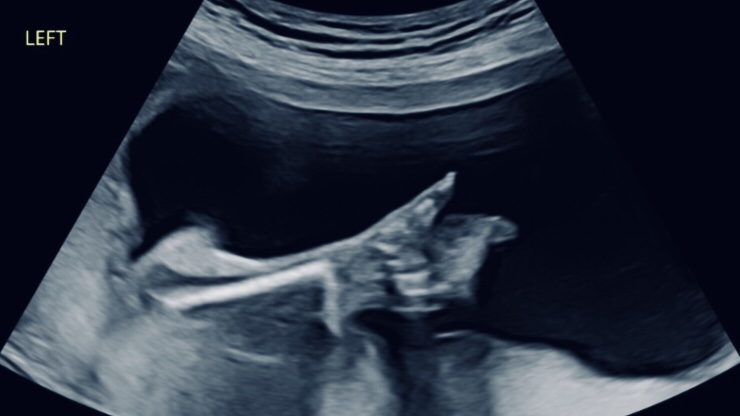

這次第二胎 Victoria 的高層次超音波檢查結果顯示一切發展狀況在符合標準的評估範圍內,只是胎動頻繁的 Victoria 還是讓 Rosa 麻麻 反覆地檢查了一整天,因此我們特別想提到台兒診所的親子友善空間,麻麻 Rosa 在檢查的時候,把拔 John 是陪著大寶 Olivia 在親子遊戲區玩耍的唷!

檢查結果報告當天就會拿到,還有詳細的說明喔!妊娠評估「中期胎檢結構篩檢」報告有文字檔案與超音波影像檔案。